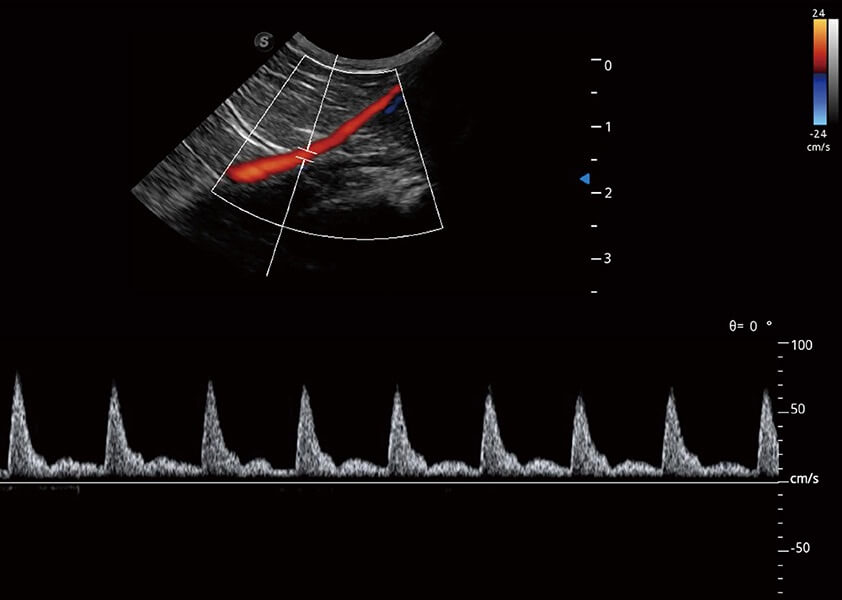

(貓)髂動(dòng)脈血流頻譜